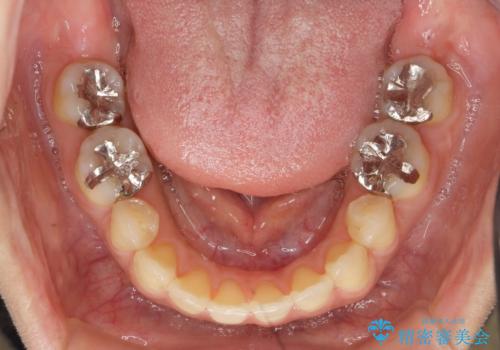

金属を白くしたい、セラミックへ